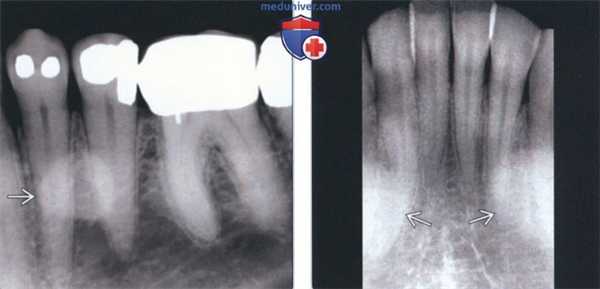

(Слева) На периапикальной рентгенограмме области средней трети корней премоляров слева определяется четко отграниченный рентгеноконтрастный участок. Такая локализация типична для нижнечелюстных валиков, хотя валики большого размера могут распространяться кзади к молярам и кпереди к резцам. Обратите внимание на отсутствие просветления на периферии. Четкие и ровные края помогают отличить валик от идиопатического остеосклероза.

(Справа) На периапикальной рентгенограмме центральных резцов нижней челюсти определяются типично выглядящие двухсторонние нижнечелюстные валики.

3. Рентгенография при нижнечелюстном валике:

• Интраоральные рентгенограммы:

о Двухсторонние хорошо отграниченные рентгеноконтрастные участки в области средней трети корней премоляров нижней челюсти

4. КТ при нижнечелюстном валике:

• КЛКТ:

о Двухсторонние экзофитные участки высокой плотности с язычной стороны в области премоляров нижней челюсти